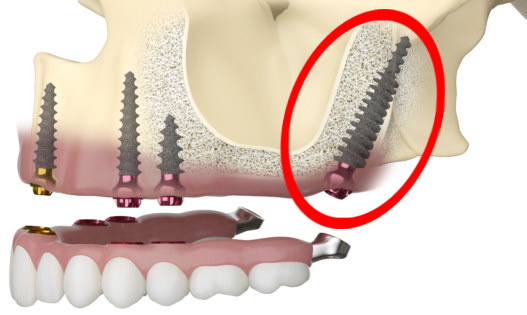

Zygomatic and pterygoid implants are both specialized dental implants designed for patients with severe bone loss in the upper jaw, but they differ significantly in their placement and purpose.

Zygomatic implants are anchored into the zygoma, or cheekbone, providing a stable foundation for dental prosthetics when there is insufficient bone in the maxillary region.

In contrast, pterygoid implants are anchored into the pterygoid plates of the sphenoid bone, located further back in the upper jaw. This placement allows pterygoid implants to provide support in areas where both the maxilla and zygoma are inadequate.

Another key difference is the surgical approach and complexity. Zygomatic implants typically require a more extensive surgical procedure due to their length and anchorage into the cheekbone.

Pterygoid implants, while also complex, are often used in conjunction with other implants to provide additional support and stability. Understanding these differences helps in selecting the most appropriate implant solution for individual patient needs.

Situational uses of zygomatic and pterygoid implants vary based on the extent and location of bone loss in the upper jaw.

Zygomatic implants are particularly beneficial for patients with severe maxillary atrophy, where the upper jawbone is insufficient to support traditional implants.

They are often employed in cases requiring full-mouth rehabilitation, providing a robust foundation for dental prosthetics by anchoring into the dense zygomatic bone.

Pterygoid implants, on the other hand, are used when there is significant bone loss in both the maxillary and zygomatic regions.

They are ideal for providing additional support in the posterior maxilla, offering stability where traditional and even zygomatic implants might not suffice. These implants are frequently used in conjunction with other implants to create a comprehensive support structure for dental prosthetics.